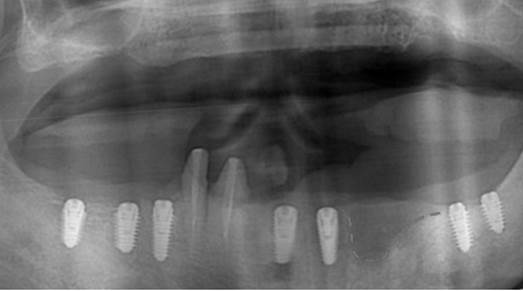

Clinical case: AFull transition from natural teeth to all-on-6 bridges

with AnyRidge implants

- Courtesy of Dr. Rabih Abi Nader, UAE -